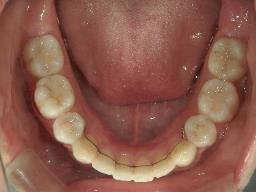

矯正歯科 治療前